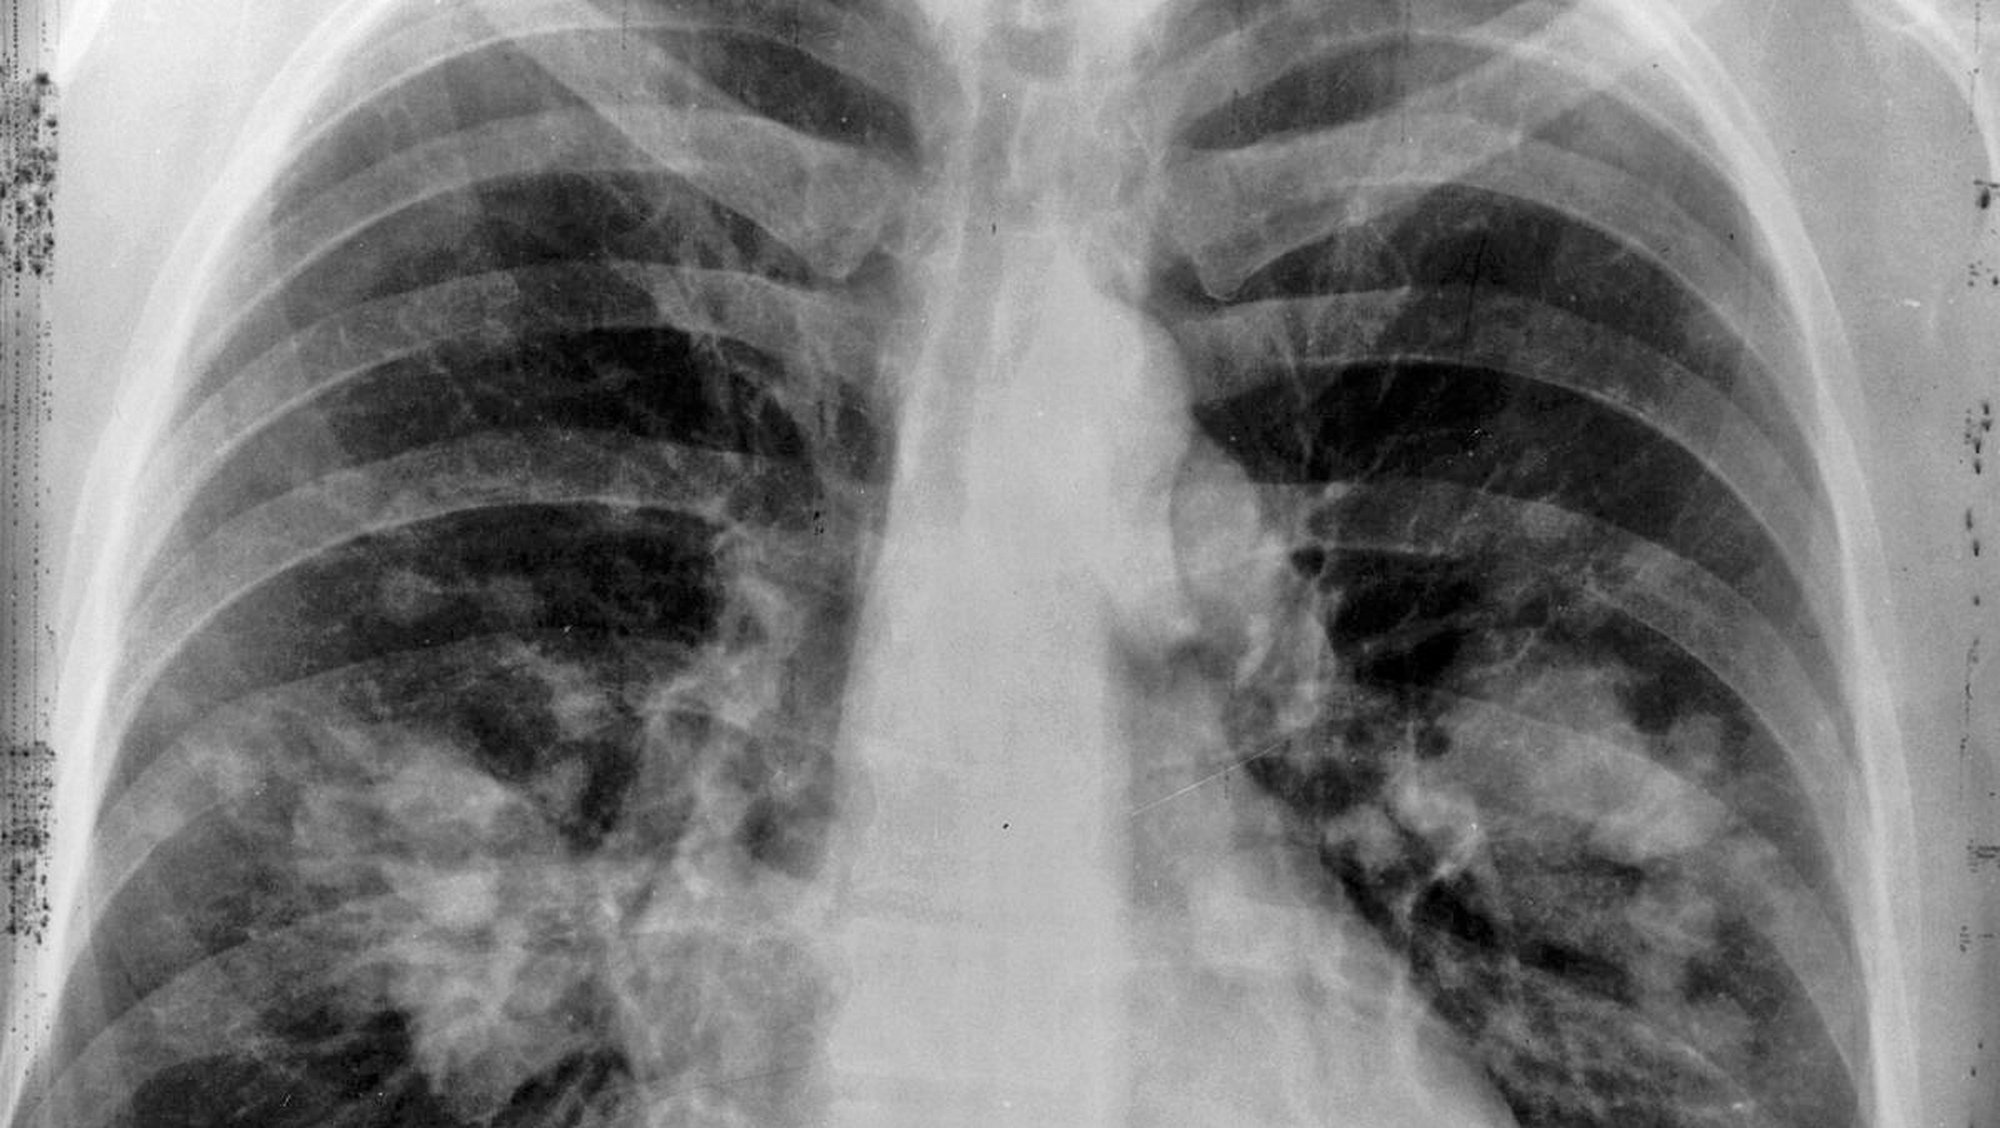

- Solunum sistemi belirtileri Bronş obstrüksiyonu yapan tümörler dispne, pnömoni

- Akciğer parenkiminin yoğun invazyonunda solunum hacmi azalması

- Plevra infiltrasyonunda ağrı